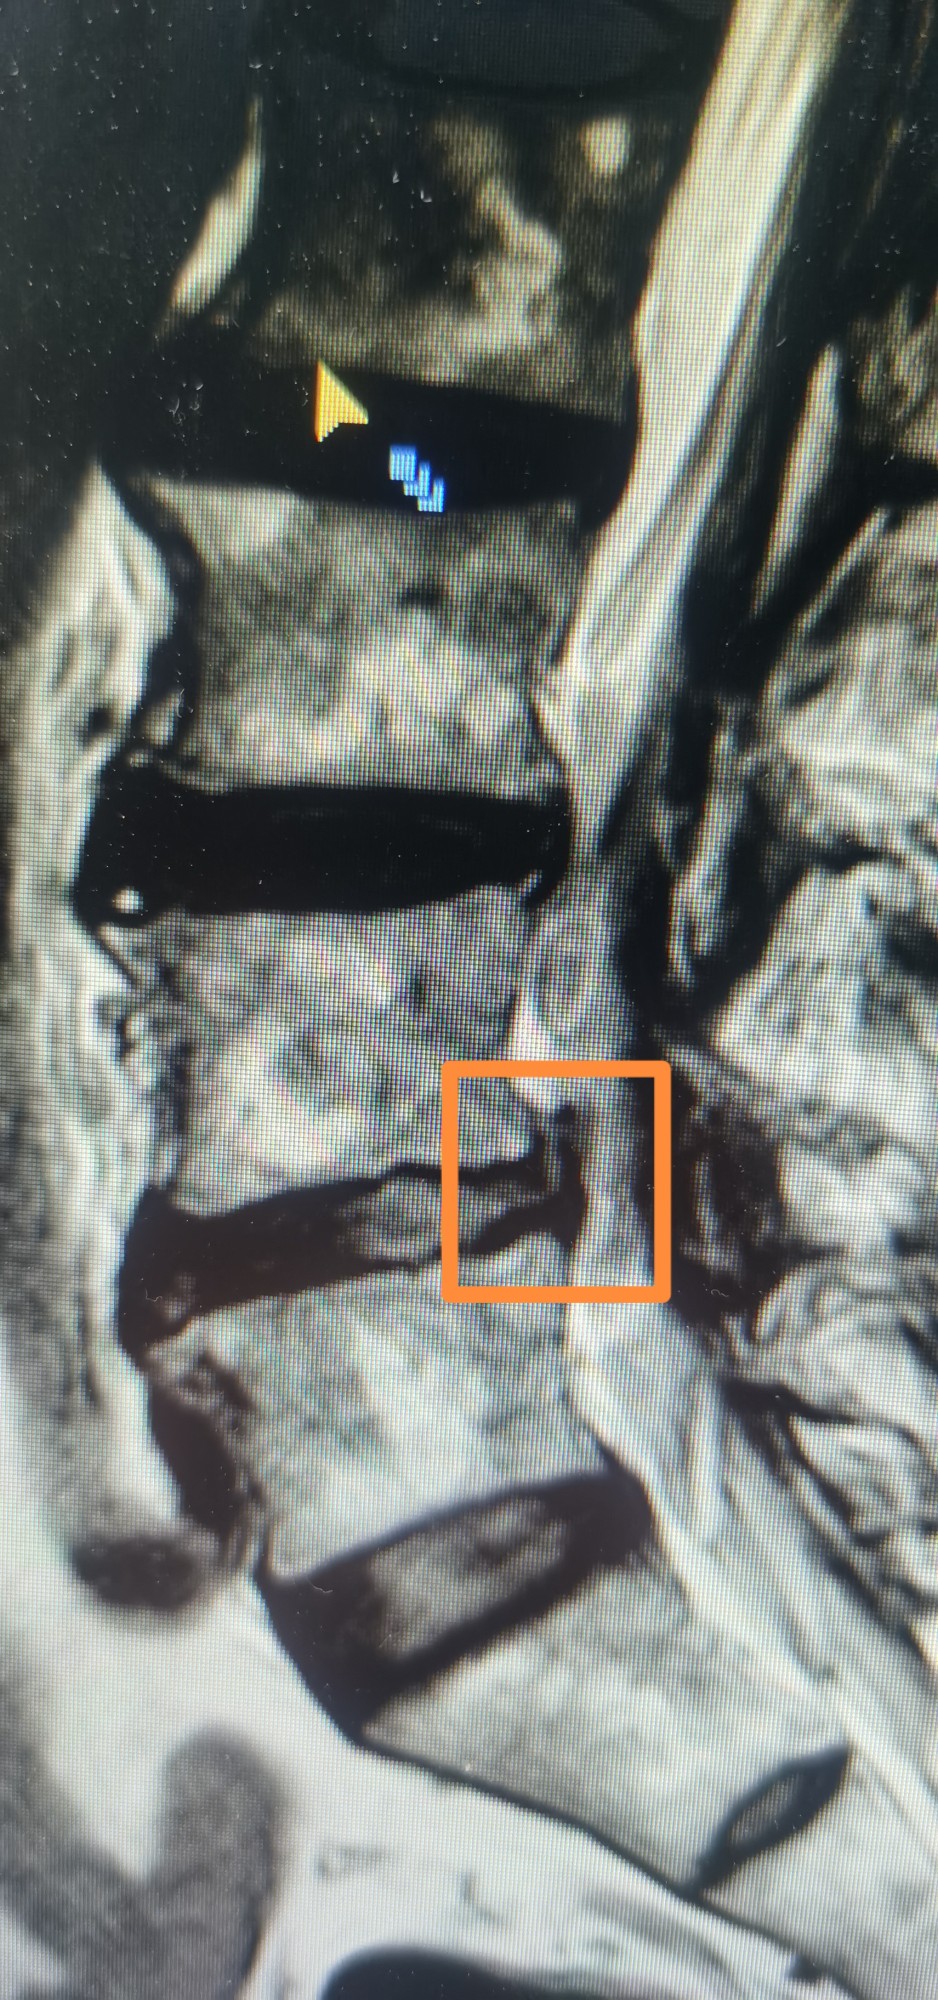

磁共振和CT椎间盘脱出2

椎间孔镜取出大块脱出的椎间盘